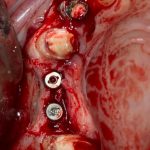

Я зафиксировал костный блок практически без адаптации на несколько винтов. Обрати внимание, что винты находятся в зоне, где не планируется установка имплантатов. Фиксация должна быть надежной, поскольку мне еще предстояла подготовка лунок для имплантатов. Трех винтов для этого вполне достаточно.

Дальнейшая адаптация костного блока свелась к сглаживанию острых краев. После чего я приступил к подготовке лунок и установке имплантатов.

Установка имплантатов.

Напомню, что для этой работы я выбрал субкрестальные имплантаты Ankylos C/X. Они прекрасно сочетаются с любым методом остеопластики.

Я не планирую установку супраструктур или коронок, поэтому на уровень первичной стабильности можно положить болт. Даже наоборот — чем меньше крутящий момент при установке, тем лучше. Для имплантатов Ankylos и подобных им, это особенно важно. В общем, момент силы при установке — не более 10-15 Нсм.

Ремарка: имплантаты с предустановленными имплантодержателями хороши тем, что с ними легко контролировать позиционирование имплантатов. В случае с Ankylos С/Х - еще и крутящий момент. Имплантодержатель должен отсоединяться от имплантата с легким щелчком. Если его клинит, и тебе приходится прикладывать для этого усилия, то ты, однозначно, превысил момент силы во время установки имплантата. Следовательно, жди проблем.

Глянем на то, что получилось: